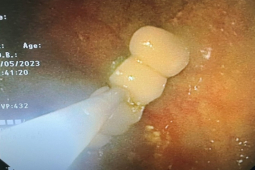

Sau 30 ngày điều trị tích cực, phối hợp hội chẩn liên khoa Dinh dưỡng, Y học cổ truyền, bệnh nhân đã cai được máy thở, được thay canuyn mở khí quản 2 nòng, thể trạng cải thiện và được xuất viện.

Sau 1 tháng bệnh nhân C. được tái khám theo hẹn, thể trạng tiến triển tốt, tình trạng nhiễm trùng ổn định, phản xạ ho khạc tốt, được rút canuyn mở khí quản, theo dõi 1 tuần sau đóng lỗ mở khí quản, mọi chỉ số cận lâm sàng đều ổn định. Đến thời điểm hiện tại, bệnh nhân tỉnh táo hoàn toàn, tự thở qua mũi được xuất viện về nhà.